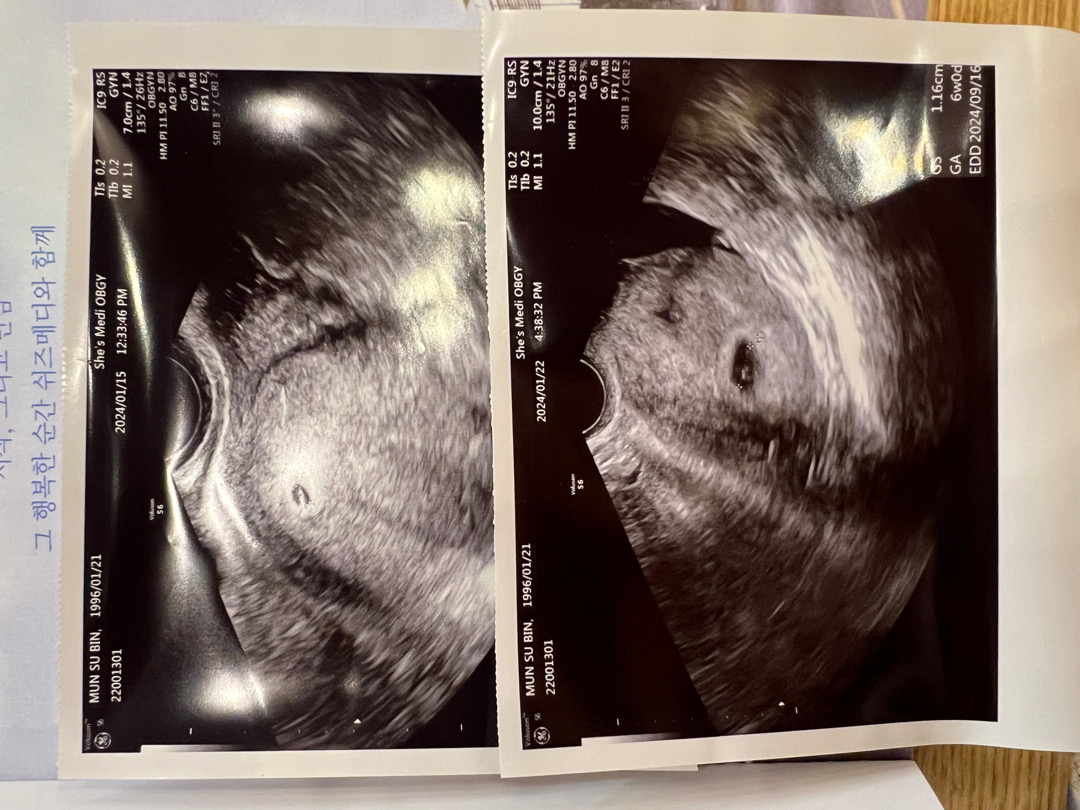

심소 못 들었어요😭

위에가 5주 2일(1/15)이였고요 아래가 1/22인데 6주0일이더라구요..ㅠㅠ 아직 심소 듣기 좀 빠른 시기여서 못 들은 거겠죠..?ㅠㅠ 다음 주에 또 오라고 하셔서 1/29 예약해뒀는데... 제발 심소 잘 들려주고 건강하게 만나기를.. ㅠㅠㅠ 조금 불안하네요😭